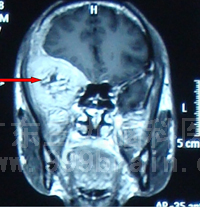

治疗前可见颅内转移癌(红色箭头处)